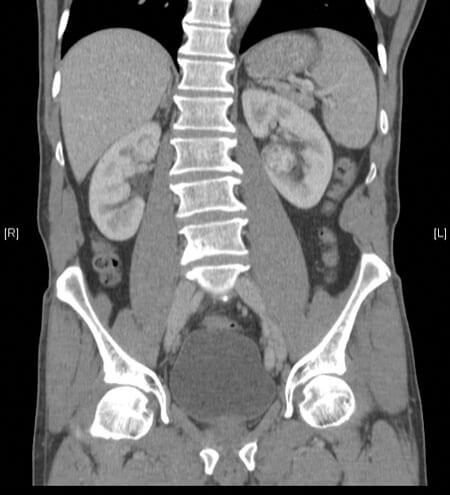

Figure 1: Endophytic left renal tumour removed at robotic partial nephrectomy.